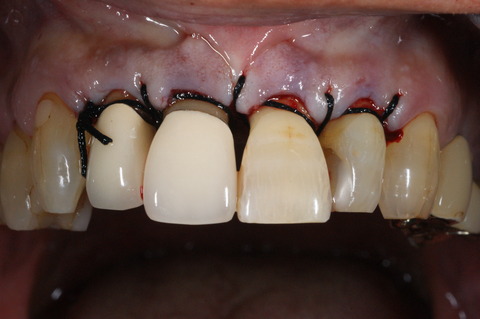

493.歯周外科(1) 2023年10月25日 15:30 この症例は歯を歯周病から救うために、やむなく外科処置を行って通常の歯石除去では取り切れない、歯周ポケット約8mmの原因になっている炎症性物質(歯垢、歯石,細菌、不良肉芽など)を廓清したものです。(大) 「歯周治療」カテゴリの最新記事 「外科処置」カテゴリの最新記事 < 前の記事次の記事 > コメント コメントフォーム 名前 コメント 評価する リセット リセット 顔 星 投稿する 情報を記憶